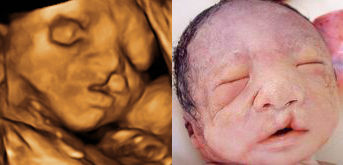

B超是利用超声波探测技术对人体脏器进行检查,没有电离辐射、电磁辐射,相对安全,因此用于对胎儿的结构进行检查就有突出的优势。B超从最早的普通B超,到彩色B超,再到今天的4维彩超。4维超声技术就是采用3维超声图像加上时间维度参数,这项技术能够实时获取三维图像,超越了传统超声的限制。它提供了包括腹部、血管、小器官、产科、妇科、泌尿科、新生儿和儿科等多领域的多方面的应用。尤其在对胎儿的产前筛查方面更是立下了汗马功劳。

现代的产科,产科医生再有经验,也不能看到宫内胎儿的形态、脏器,已经不能离开B超检查了,七个月之前的各项检查都与筛查胎儿畸形有关,11-13周时胎儿颈部皮肤透明层是筛查21-三体的重要指标;22周左右时胎儿畸形的排查;24-28周时胎儿先天性心脏病的检查。七个月之后30-32周时胎儿畸形的补漏筛查;37周时胎儿宫内安危的筛查(包括脐带缠绕、羊水多少、胎盘功能、脐血流比值的测定、生物物理评分等)。因此产科B超在提高出生人口质量、维护母婴安全方面起到了令世人瞩目的作用。文/赵天卫